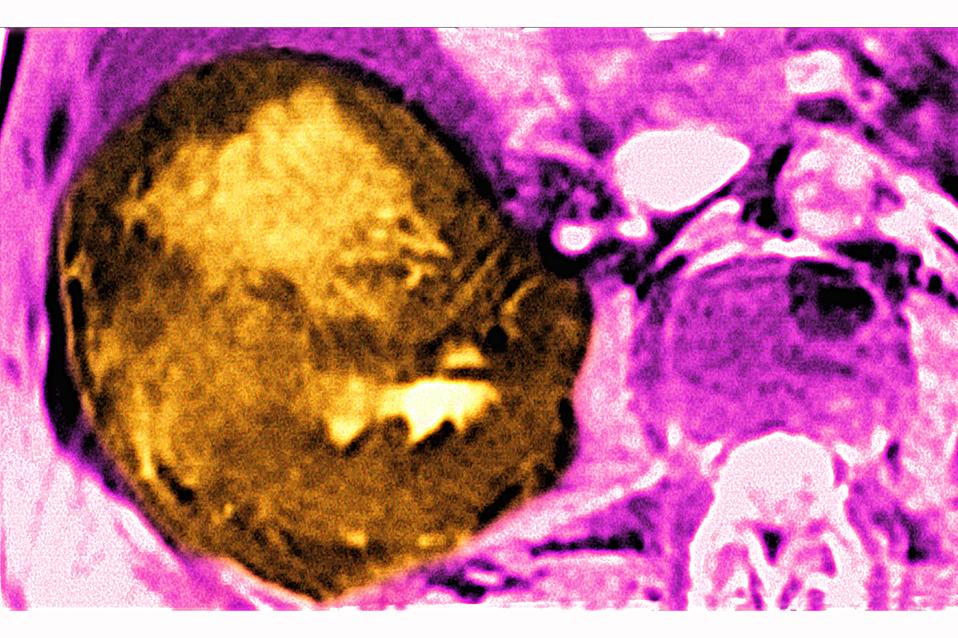

Cancer of the liver, seen in a radial cross-section abdominal scan. (Photo by: BSIP/Universal Images Group via Getty Images)